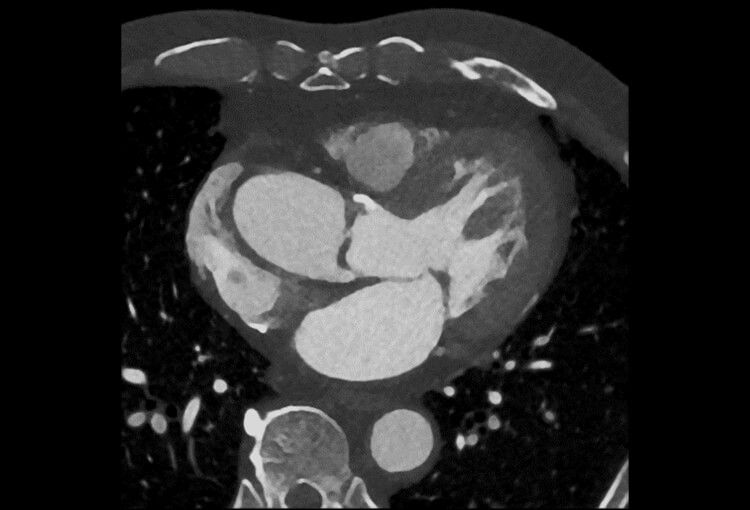

120 kV / 30 mAs / 1mm

Before FBP (Noise 150) VS After ClariCT.AI (Noise 49) 67% Denoising